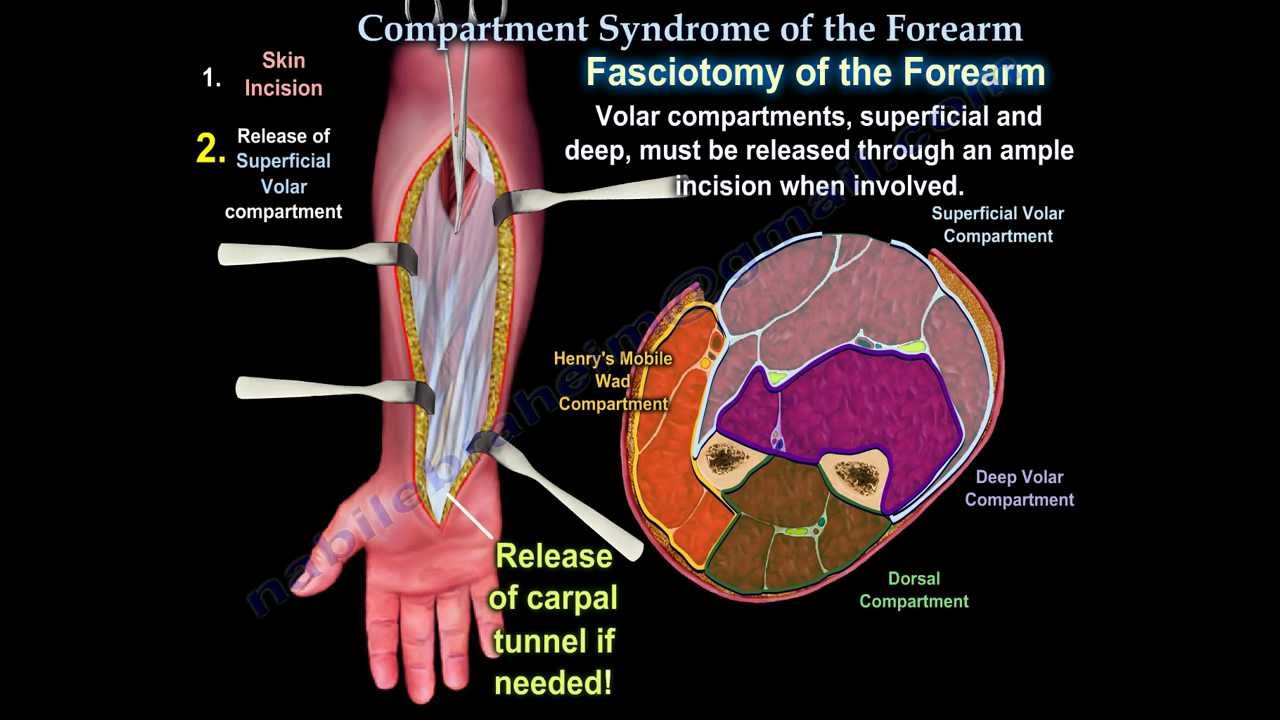

Compartment Syndrome Of The Forearm Everything You Need To Know Dr

Compartment Syndrome Acute Chronic Anatomy And Operation

Compartment Syndrome Acute Chronic Anatomy And Operation